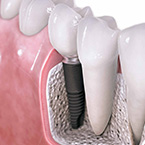

Los implantes son raíces artificiales de titano que se fijan en el hueso y sobre ellas colocamos las coronas que sustituyen los dientes perdidos. Es la mejor alternativa terapéutica para devolver la estética y función de un diente. Existen numerosos tipos de tratamientos dentro de esta especialidad: